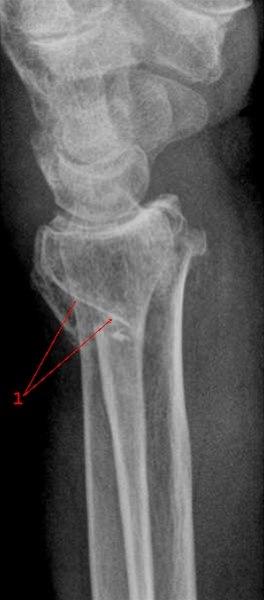

Brudd i nedre del av radius, mindre enn 4 cm fra nedre ende av beinet, betegnes på fagspråket som distalt radiusbrudd eller fractura radii typica. Denne bruddtypen kan medføre at de to bruddendene spriker eller blir forskjøvet i forhold til hverandre, men bruddet kan også være uten forskyvning av bruddendene. I unntakstilfelle kan bruddet skade nerver som ligger nær.

Brudd i håndleddet er den vanligste bruddskaden som forekommer. Bruddtypen er hyppigst hos eldre kvinner, men det er heller ikke uvanlig hos yngre personer. Cirka 90 prosent av bruddene innebærer at det ytterste bruddstykket er skjøvet opp (dorsalt, mot håndryggssiden) - denne bruddtypen kalles også Colles brudd (se tegningen over).

Røntgenbilder tatt forfra og fra siden bekrefter diagnosen (se over). Man ser etter feilstillinger, om det er brudd som innbefatter selve håndleddet, om det er ujevnheter i leddspalten, eller om det foreligger andre beinskader.